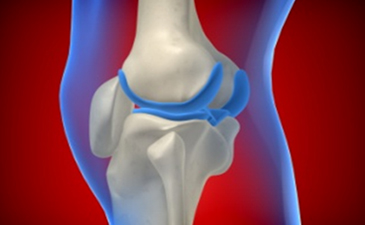

슬개골인대손상이란?

슬개골인대손상은 무릎 주위 인대가 강한 외부의 충격이나 무리한 사용으로 찢어지거나 파열되어 일상생활에 불편을 주는 질환입니다. 무릎 인대는 많이 사용하면 할수록 약해져 부분적으로 손상을 일으키기 쉬우며 슬개골인대손상은 무릎 옆쪽인대 손상, 전방 십자인대 손상, 후방 십자인대 손상으로 나누어집니다.